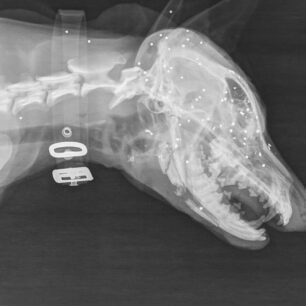

Ήταν πυροβολημένο στο πρόσωπο με καραμπίνα εξ επαφής, είχε διαλυθεί η γναθος, είχε πολλαπλές κρανιοεγκεφαλικες κακώσεις και η κατάστασή του ήταν ιδιαίτερα κρίσιμη.

Υπήρχε και δεύτερος πυροβολισμος στη σπονδυλικη στήλη.

Δόθηκαν οι πρώτες βοήθειες με την ελπίδα να σταθεροποιηθει, στείλαμε ακτινογραφιες σε κτηνιατρους, ώστε μετά να συζητηθεί τι χειρουργικές επεμβάσεις θα χρειαστούν.